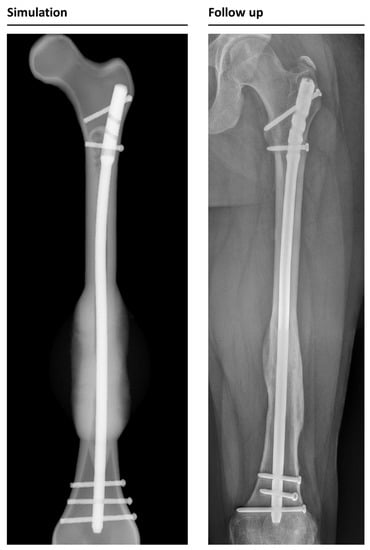

The simulation classified 26 cases as “healing”, while it categorized 6 cases as non-unions. In retrospective comparison with the clinical outcomes, the simulation correctly predicted 23 uncomplicated healing fractures. Three patients would have been expected to heal according to the simulation, but clinically turned out as non-unions (false negatives). Four out of six predicted non-unions were correctly recognized by the simulation, but two cases were wrongfully diagnosed as developing non-unions (false positives). This means the simulation correctly predicted the right outcome in 85% of the cases (Figure 4 and Figure 5).

Figure 5. Example of a correctly simulated non-union fracture. The postoperative X-ray (picture 1) is used to build a 3D reconstruction (picture 2). The simulation correctly predicts a biomechanically induced non-union (picture 3). A retrospective comparison to a follow-up X-ray on day 178 after surgery shows similar callus formation and no healing, resulting in a consecutive revision surgery (picture 4).